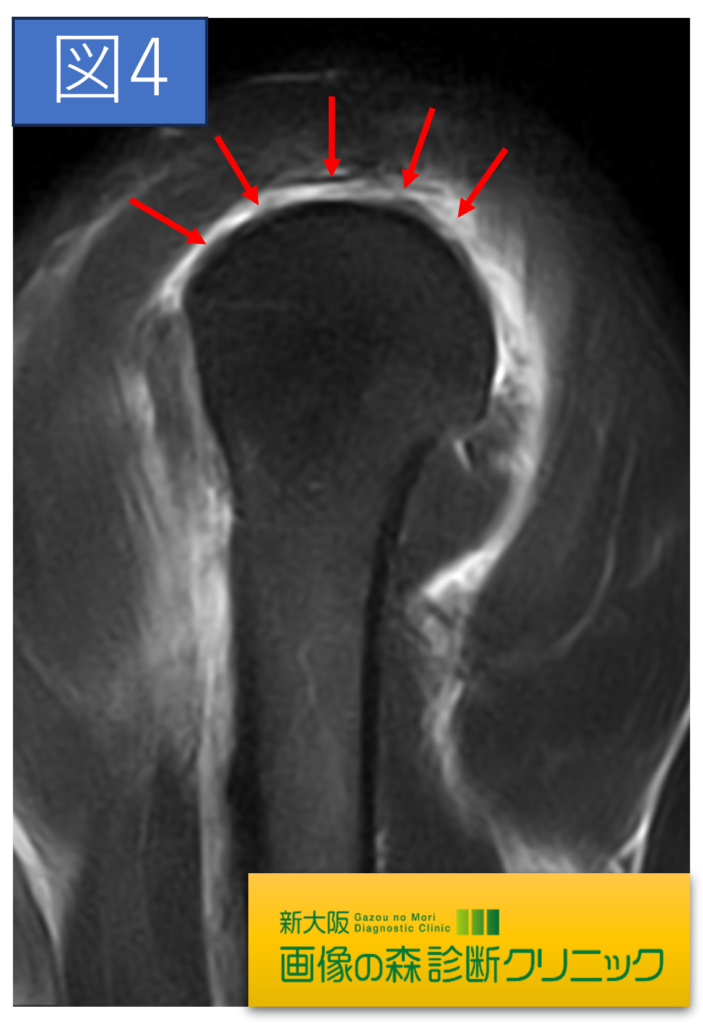

肩関節正常画像(矢状断像)

肩関節症例画像(矢状断像)

症例画像から図1~図4は棘上筋腱の画像です。□内に棘上筋腱の損傷を示します。正常では靱帯や腱は黒く描出されますが、損傷では白く高信号に描出されます。棘上筋腱損傷は、加齢による変性や転倒・スポーツ・仕事などによる外傷が原因となります。

症例画像から図1~図4は棘上筋腱の画像です。□内に棘上筋腱の損傷を示します。正常では靱帯や腱は黒く描出されますが、損傷では白く高信号に描出されます。棘上筋腱損傷は、加齢による変性や転倒・スポーツ・仕事などによる外傷が原因となります。